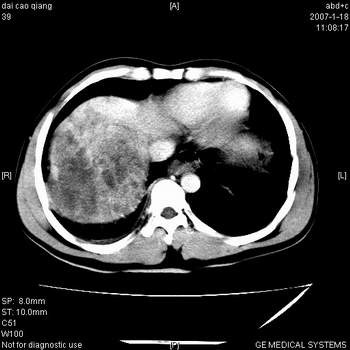

符合巨块型肝癌表现:

1、平扫低密度,增强后表现为快进快出。

2、动脉期可见迂曲的动脉供血血管

3、并可见门静脉右支癌栓形成

4、可见假包膜

5、腹主动脉旁结节影,考虑肿大淋巴结。

肝右叶巨大不均匀低密度肿块,前缘有假包膜,增强明显的呈快进快出表现,门脉右支有癌栓,病人虽然年轻但还是首先考虑肝右叶巨块形肝癌,病人血象高只能说有合并感染。不支持肝脓肿。